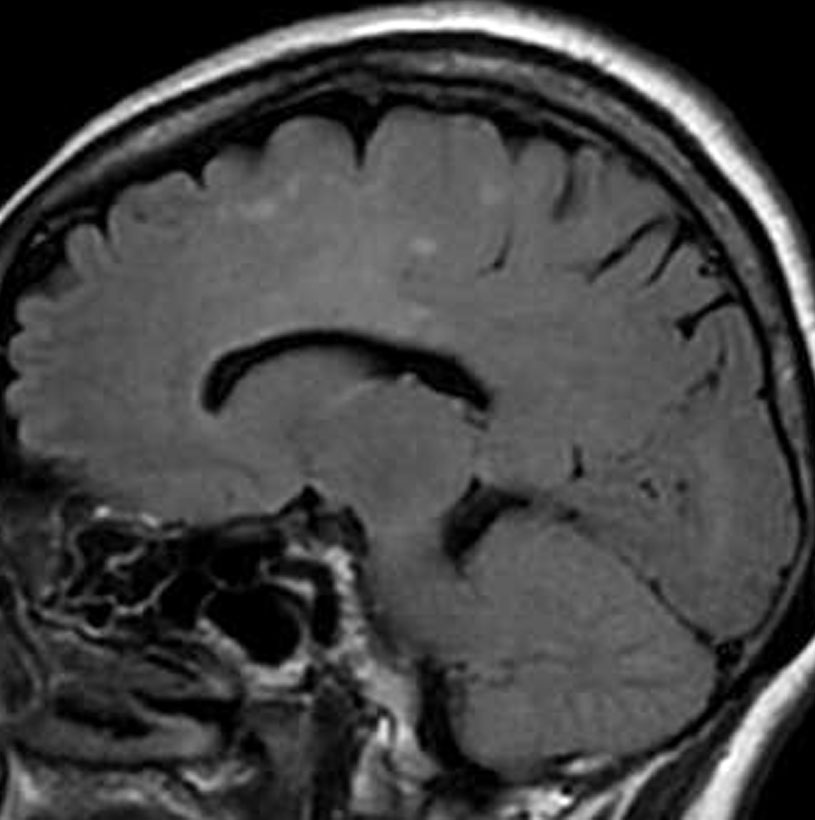

左側頭葉のびまん性星細胞腫です。左側のT1強調ガドリニウム像ではほとんど腫瘍は見えません。真ん中のT2強調画像でも見づらいです。右側のフレア画像で白くにじんでいるところに腫瘍があります。どこまでが腫瘍の境界なのかがはっきりしない腫瘍です。左の海馬(記憶の中枢)を侵し,とてもゆっくり大きくなるタイプで,この患者さんは10年以上治療をしないで経過を見ています。全摘出できない星細胞腫グレード2です。